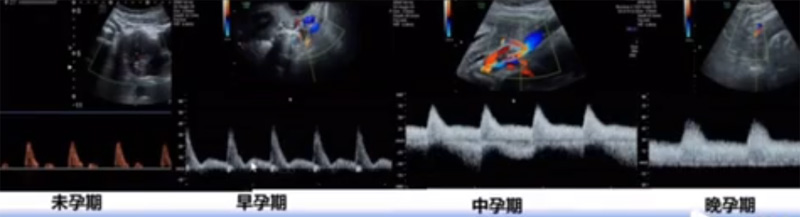

位於輸卵管的後下方,子宮兩側的後上方;借卵巢係膜與子宮闊韌帶後層相連。正常成人卵巢約4x3x2cm,跟睾丸的數值差不多,都是性器官,絕經後卵巢萎縮變小、變硬。所以絕經後婦女很難找到卵巢,主要功能:生殖和內分泌功能分泌性激素。女性的第二性征。女性內生殖器的血管分布,動脈有子宮動脈,卵巢動脈,陰道動脈,陰部內動脈。靜脈它是與動脈伴行。重要了解的是子宮動脈,子宮動脈是髂內動脈前幹的重要分支,妊娠時候血流速度會增加的,為無創性檢查胎盤血管阻力的方法。未孕期頻譜為高阻力低舒張波形;正常妊娠時血流速度增加,血流阻力下降。